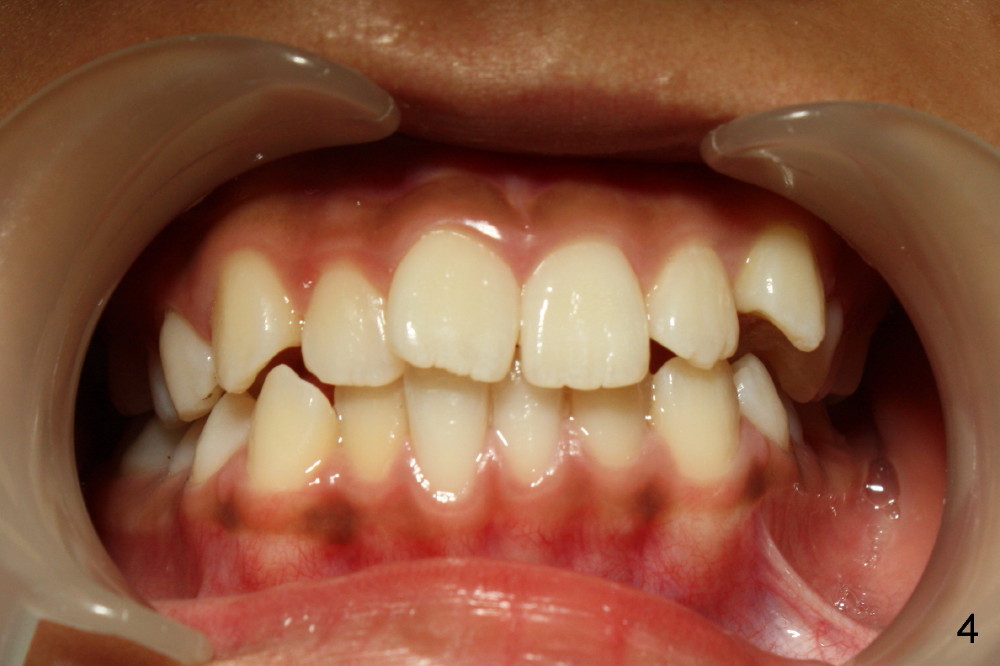

Now at the age of 12 years 10 months, #2 has erupted whereas #15 remains unerupted (Fig.2).

There is basically Class I occlusion in molar and canine regions bilaterally (Fig.3,5). Crowding is severe in the anterior area (Fig.4).